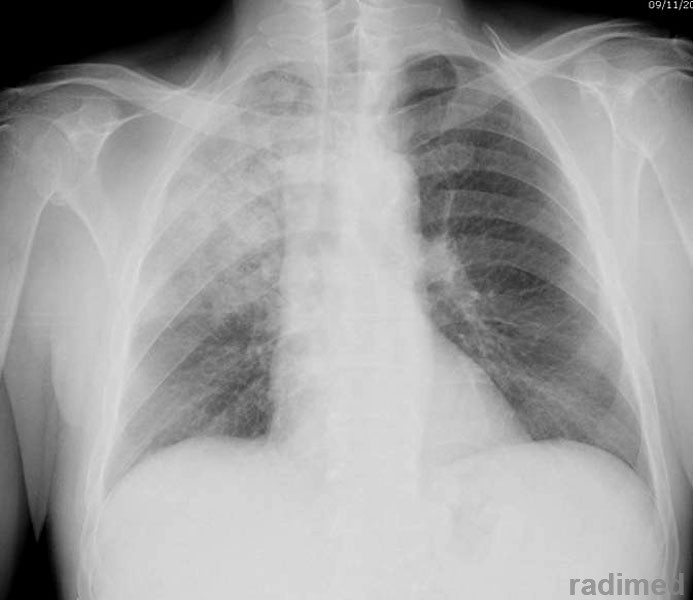

Ejercicios respiratorios previenen la neumonía postoperatoria

Una sesión preoperatoria de 30 minutos para educación en fisioterapia respiratoria redujo a la mitad las complicaciones pulmonares. BMJ, 24 de enero de 2018

Nuevas guías para neumonía intrahospitalaria proponen acortar la duración del tratamiento

IDSA & ATS, 14 de julio de 2016